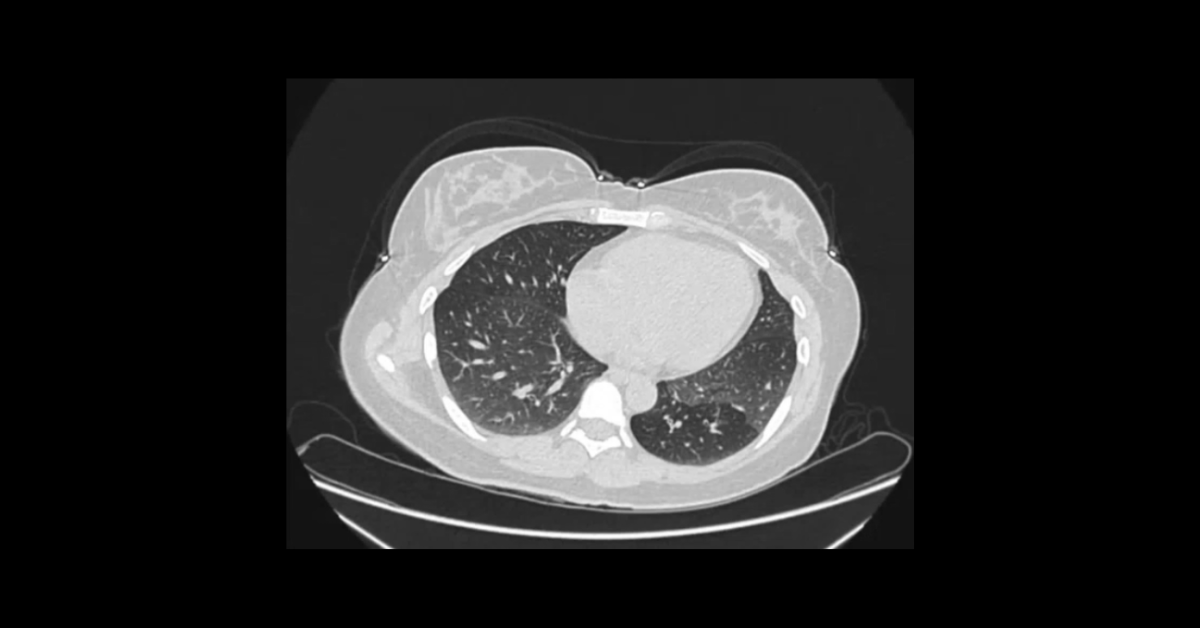

Cases of granulomatous and cavitary pulmonary processes with demonstration of their associated complications and diagnostic pitfalls.

1. Understand important pitfalls in the diagnosis of cavitary lesions.

2. List the complications of cavitary lung lesions.

3. Learn the diagnostic significance of satellite nodules and “tree-in-bud.”